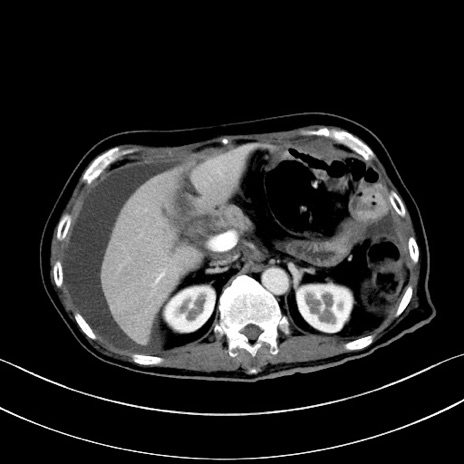

症例28(横断像)

【症例】60歳代男性

【主訴】嘔吐

【現病歴】胃癌にて胃全摘後。食思不振が悪化し、夜中に嘔吐することがある。

【既往歴】胃癌、胃全摘、脾摘、胆摘後

【データ】WBC 5900、CRP 10.56